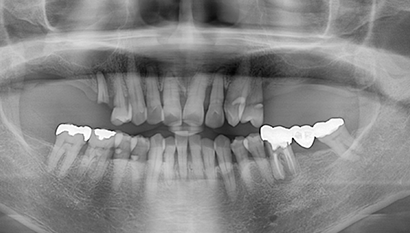

W Dental Clinic Before & After

治療前後の写真

Before

After

上顎洞挙上術です。